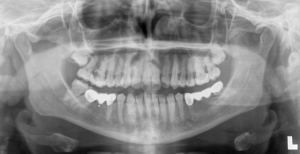

Step 6 – OPG (Full Mouth X-Ray)

A full mouth X-Ray will capture a panoramic radiograph of all your teeth. This is required before conducting Orthodontic tooth movement to detect any underlying conditions such as caries or root infections. Fillings or root canal treatment will be required to restore the integrity of any affected tooth or teeth before staring any Orthodontic treatment or cosmetic dentistry.

“The OPG also detects the underlying jaw bone density because good bone health is important for conducting Orthodontic tooth movements!”- Dr. Vivek Aithal Orthodontist and Invisalign Specialist